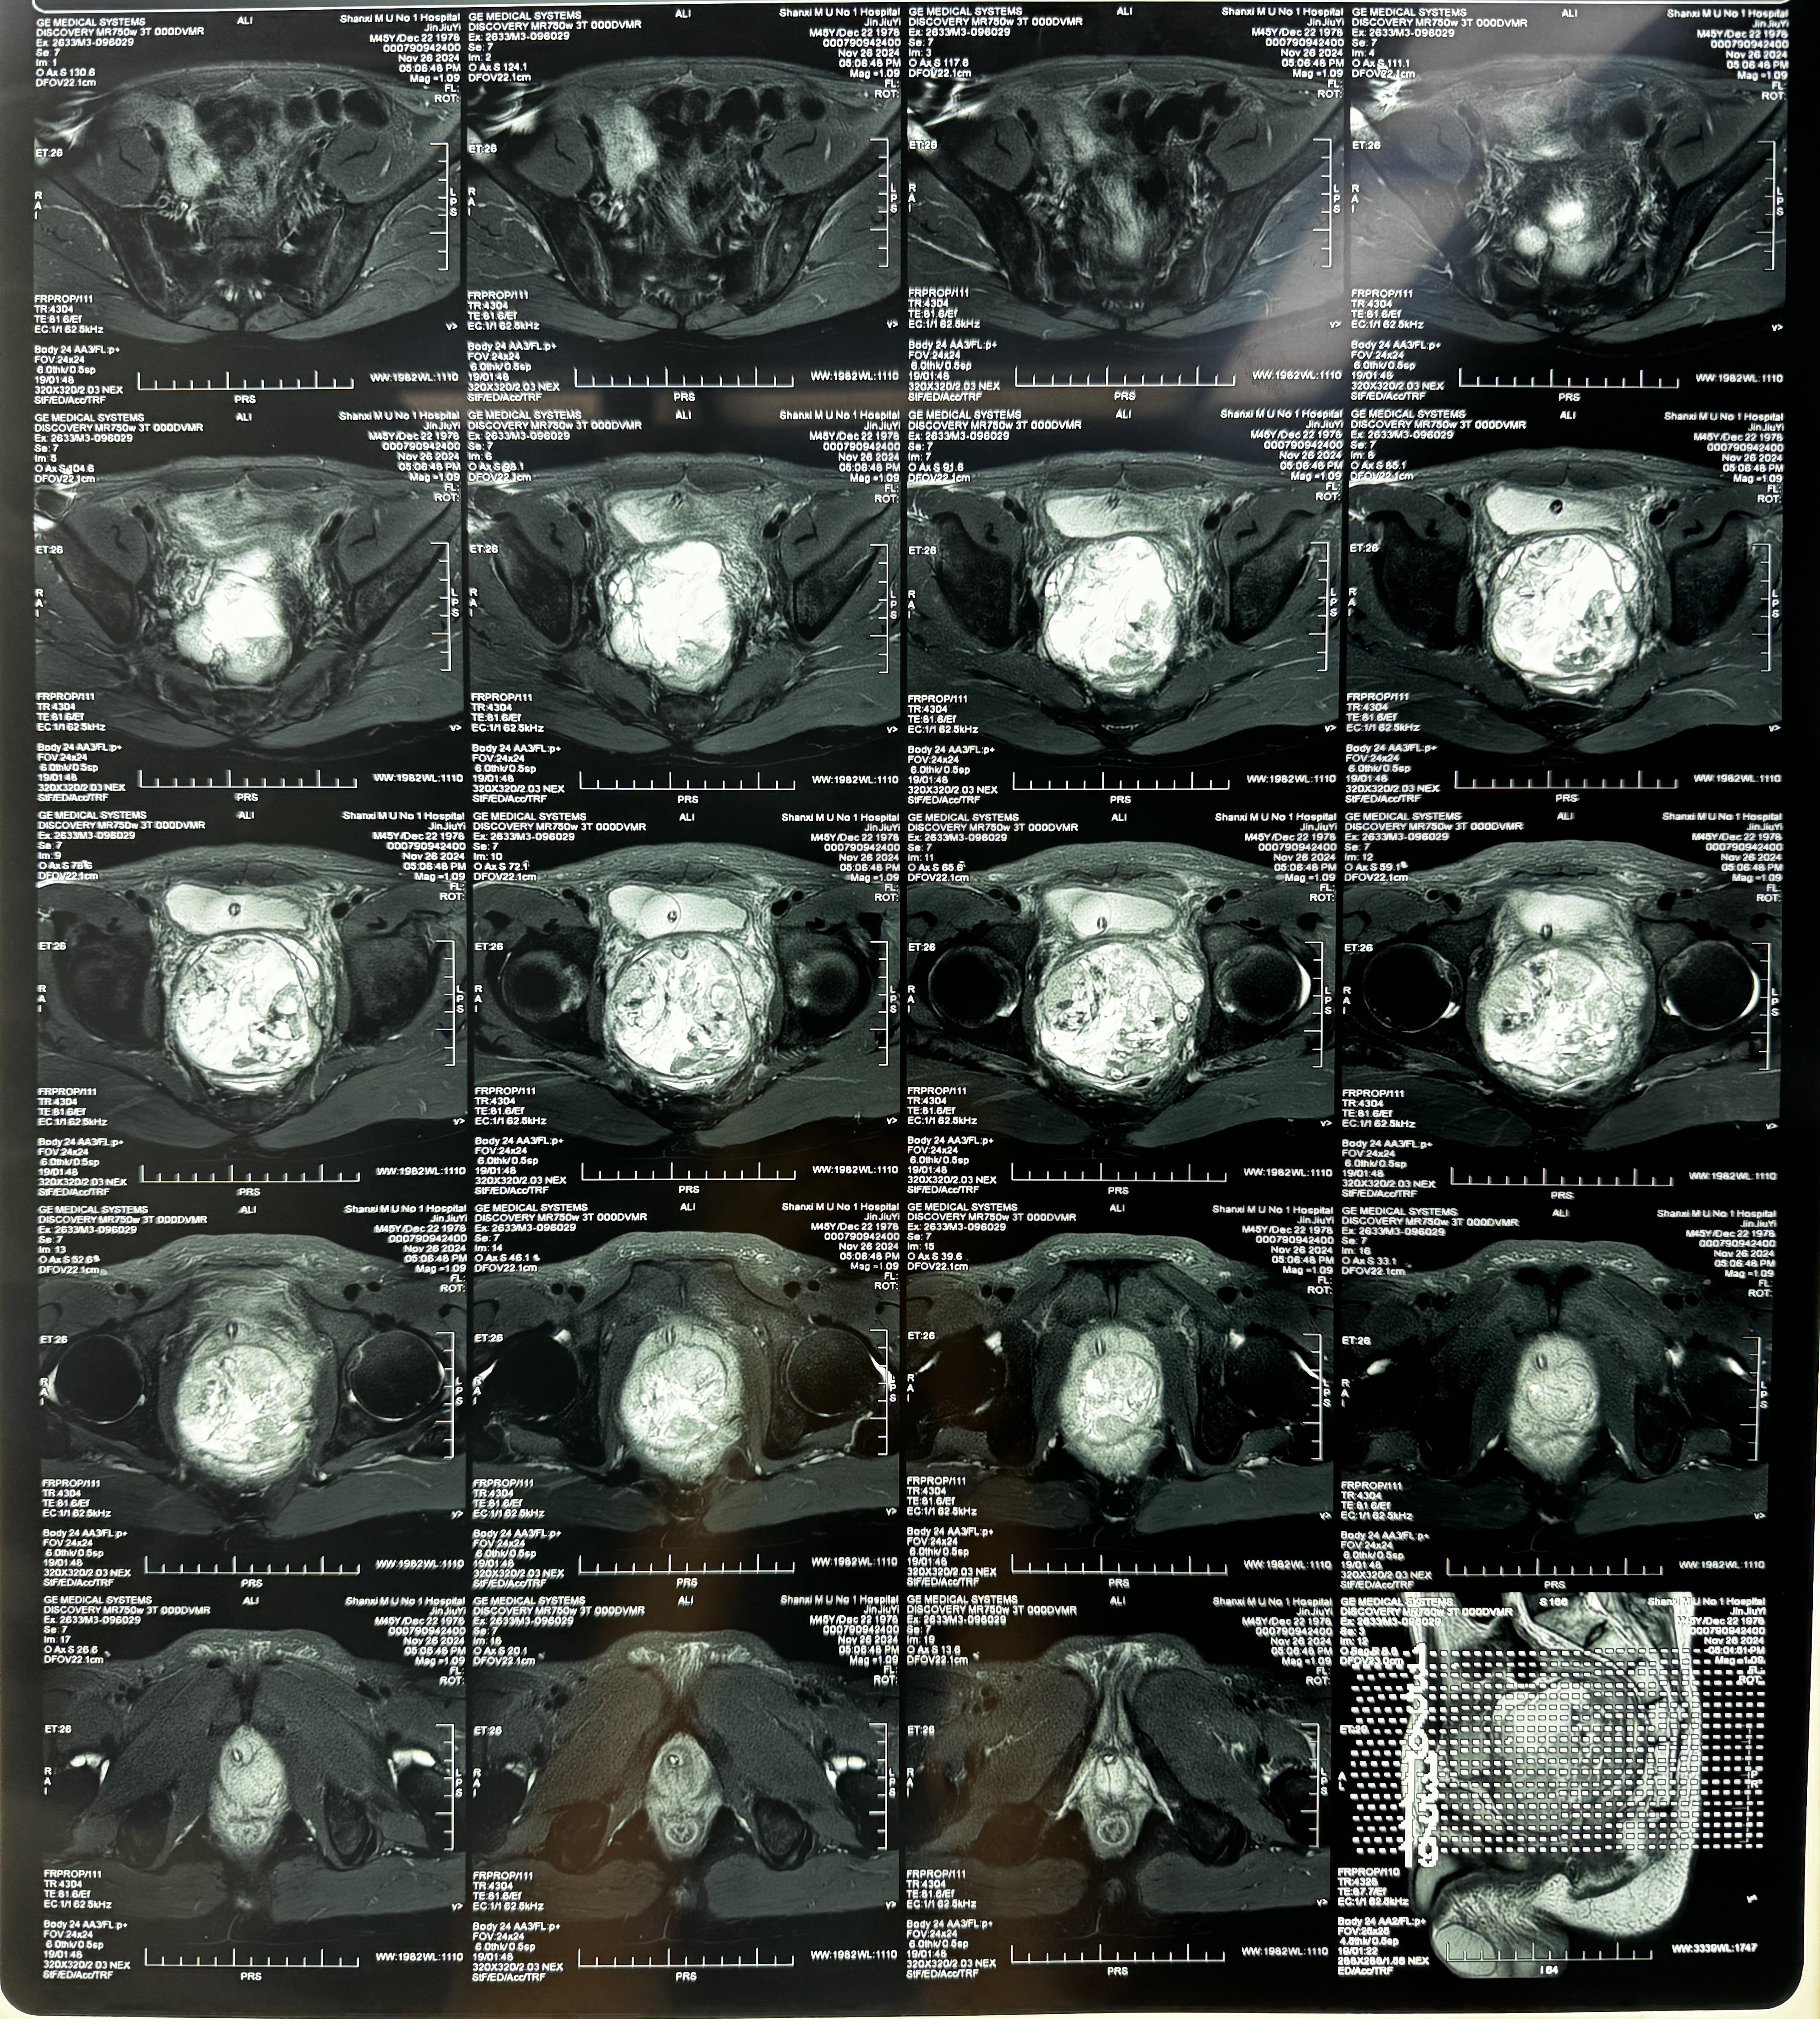

▲患者影像資料

患者兩月前出現(xiàn)無明顯原因排尿困難,在當(dāng)?shù)蒯t(yī)院行前列腺核磁,提示前列腺體積增達(dá)并混雜信號。為進(jìn)一步明確診斷赴山西醫(yī)科大學(xué)第一醫(yī)院就診,入院后出現(xiàn)排便困難,核磁共振顯示:前列腺巨大肉瘤(10×6×8cm),累及直腸及雙側(cè)精囊。后于院內(nèi)行骼內(nèi)動脈栓塞術(shù),排便困難緩解。行前列腺穿刺活檢1-8針均見腫瘤,病理結(jié)果顯示前列腺腺癌,伴壞死。診斷明確,存在手術(shù)指征。經(jīng)與患者及家屬溝通并協(xié)商一致,決定行機(jī)器人輔助腹腔鏡下前列腺肉瘤根治性切除手術(shù)。